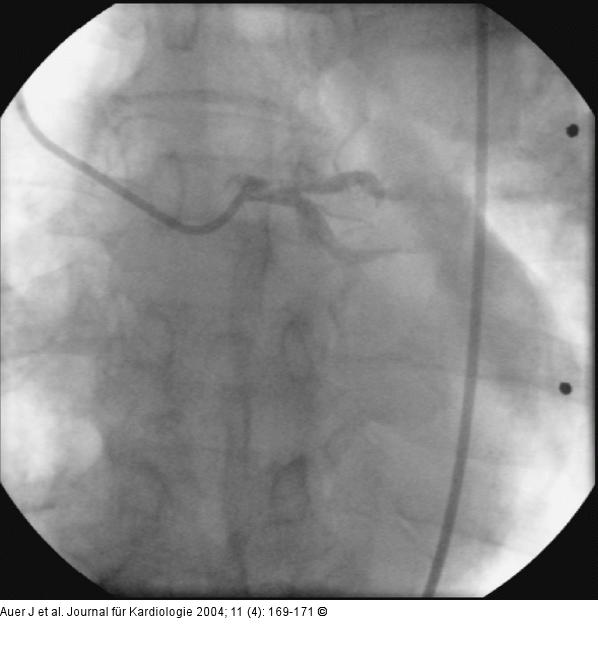

Abbildung 3: Akutes Koronarsyndrom - Stenose der linken Herzkranzarterie Stenosierung im Hauptstamm der linken Herzkranzarterie |

Abbildung 3: Akutes Koronarsyndrom - Stenose der linken Herzkranzarterie

Stenosierung im Hauptstamm der linken Herzkranzarterie |